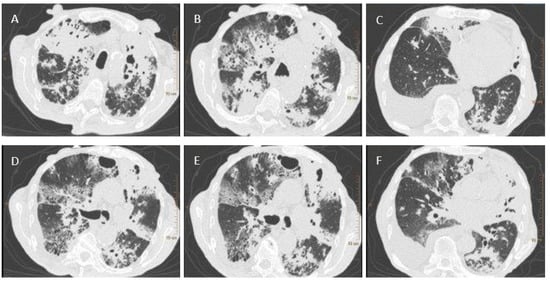

A test for SARS-CoV-2 was performed using a throat and nasal swab taken on 27 May 2020. The Vitassay qPCR SARS-CoV-2 test was positive for SARS-CoV-2 RNA. A chest X-ray revealed bilateral areas of confluent parenchymal and interstitial densities in the lungs, predominantly in the upper and middle fields. Computed tomography, completed on 28 May 2020, showed lesions typical of pulmonary tuberculosis (Figure 1). Antimycobacterial treatment was initiated empirically in the following scheme: isoniazid (INH), rifampicin (RMP), pyrazinamide (PZA), and ethambutol (EMB).

Figure 1. Figure 1. Chest CT scans. (A)—parenchymal-atelectatic lesions; thick-walled cavities filled with masses of tissue decay in the upper lobes; (B)—parenchymal-atelectatic lesions; cavities filled with tissue decay in segment 3 of the right and left lung, with the accompanying areas of tree-in-bud-appearance in segment 3 of the left lung and in the apex of segment 6 of the right and left lung; (C)—fluid in the pleural cavity; (DF)—tree-in-bud-appearance in the apex of segment 6 of the right lung and in segments 6–9 of the left lung.

Radiological observationsChest X-ray: bilateral areas of fusing parenchymal-atelectatic densities in the lungs, predominant in the upper and middle fields

CT scans: Extensive lesions parenchymal-atelectatic; thick-walled cavities filled with masses of tissue decay in the upper lobes płuc; areas of tree-in-bud-appearance in segment 3 of the left lung and in the apex of segment 6 of the right and left lung; fluid in the pleural cavity; tree-in-bud-appearance in the apex of segment 6 of the right lung and in segments 6–9 of the left lung